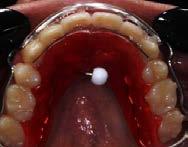

La estabilidad postratamiento a car go de retenedores termoformado Vivera retainers (Figura 8).

Se describe un caso clínico de un paciente de 14 años y 8 meses, diagnosticado con clase II esquelética, hiperdivergente, clase II molar dere cha, clase I molar izquierda, la relación canina no determinable, el overbite disminuido, el overjet aumentado, con apiñamiento moderado. Con los dientes 12 y 22 palatinizados, el 13 ectópico, con mordida abierta anterior, las líneas medias desviadas, con habito de empuje lingual. Obje tivos: mejorar el perfil facial, corrección del api ñamiento maxilar y mandibular, incorporar al arco los dientes 12,13, 22 y 23, mantener clase I molar izquierda, obtener clase I molar derecha, y canina bilateral, corrección de overjet y over bite, de las líneas medias dentales. Mejorar las relaciones esqueléticas, lograr correcta intercus pidación, la guía de desoclusión canina, la guía incisiva. Mejorar la salud periodontal. La apa ratología utilizada una rejilla lingual de Justus, brackets prescripción Roth 0.022x0.028, tubos bondeables 6´s y 7´s superiores e inferiores. Adicionalmente se realizó ameloplastía en los incisivos anteriores, extracciones de los prime ros premolares superiores, segundos premolares inferiores, terceros molares superiores e inferio res. La retención se llevó a cabo por medio de retenedores circunferencial superior con perla de Tucat y termoformado inferior. El tiempo de tratamiento fue de 2 años y 2 meses.